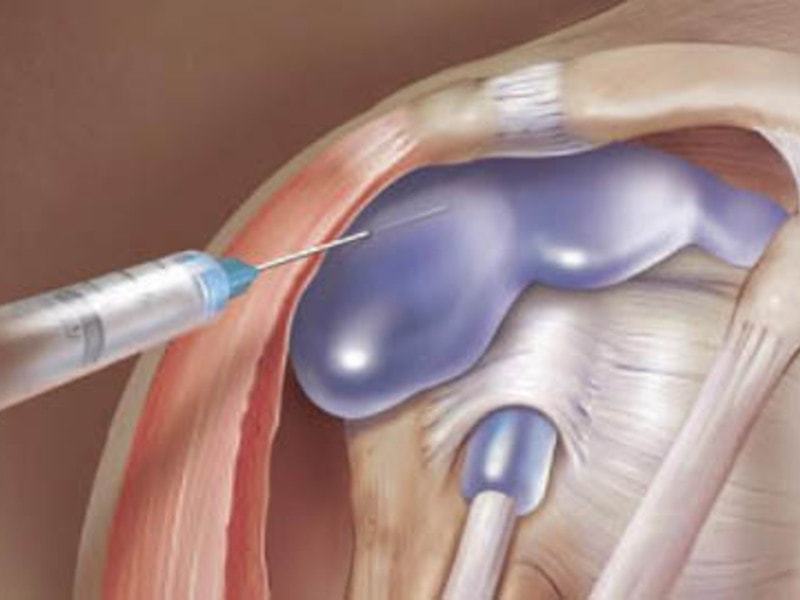

Заболевание сустава: симптомы и лечение

Раздел: Фотодневник открытий